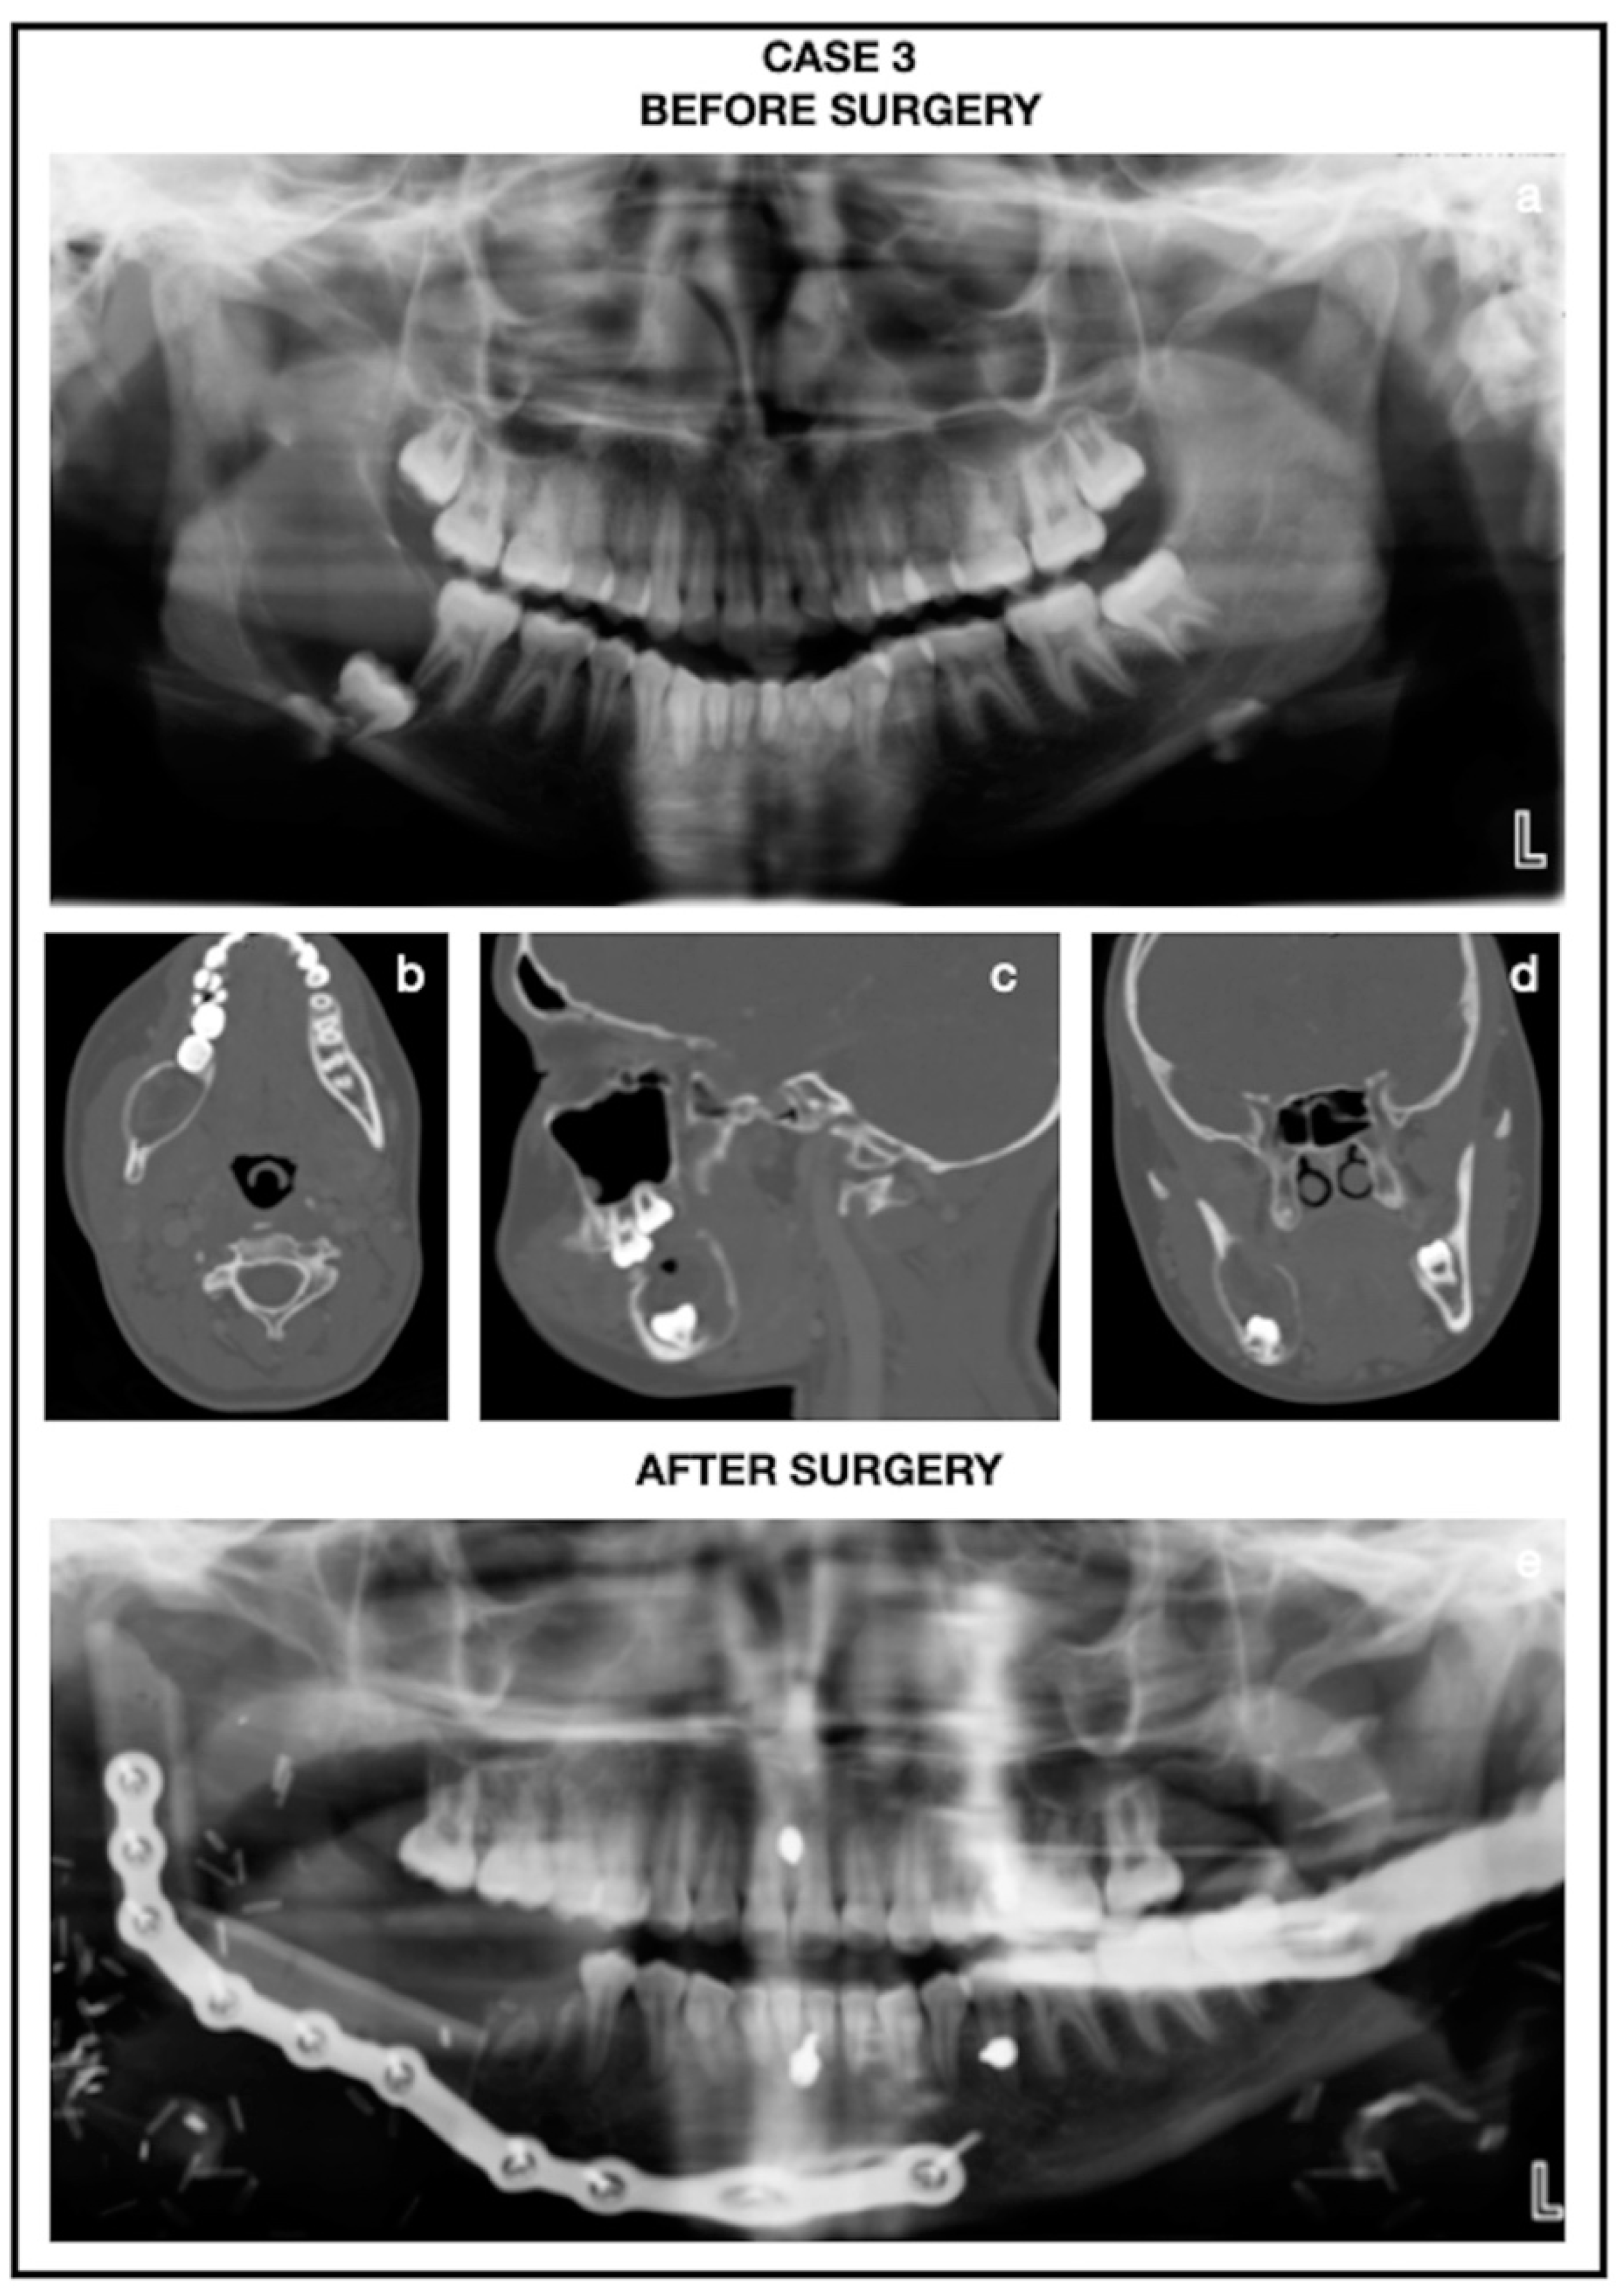

Clinical and radiological findings: A 13-year-old female with a history of the right mandibular lesion that was found 6 months ago by her dentist on a routine dental examination (Table 1). The patient denies facial swelling, numbness, and pain associated with radiolucent lesions. The patient was then referred to the Oral and Maxillofacial Surgery Department at the UMMC for further evaluation. The patient has no pertinent past medical and surgical history. The patient has no known allergies. A panoramic radiograph was taken, which showed a unilocular radiolucent lesion with the well-defined, sclerotic, and scallop peripheral margin to the right mandible involving the extending to ramus and the coronoid from the anterior ramus to the body of the mandible. The lesion was noted to be displacing tooth 48 inferiorly to the inferior border and just posterior to tooth 47 (Figure 6).

Surgery procedure: The patient was then taken to the operation room for surgery for a right segmental mandibulectomy, tracheostomy, inferior alveolar nerve graft with axogen allograft, dental extractions, removal of the right submandibular gland, and reconstruction with fibula free flap by plastic surgery.

Following up: Post-operative panoramic radiograph showed a fibula graft with hardware intact extending to the right glenoid fossa. CT imaging revealed an appropriately healing fibular graft, but no new condylar bony growth was noted on imaging. Panoramic radiograph showed bony growth to the tip of the fibula graft with neo-condylar formation (Figure 6 and Figure 7).

Figure 6. CBCT images of case 3. (a) Panoramic image before surgery. (b) Axial, (c) Parasagittal, and (d) Coronal slice of CBCT image before surgery. (e) Panoramic image after surgery.

Figure 7. CBCT images of case 3. (a) Axial, (b) Parasagittal, and (c) Coronal slice of CBCT image 6 months after surgery. (d) 3D reconstruction view of CBCT image 6 months after surgery. (e) Panoramic image showed a fibula graft with hardware intact extending to the right glenoid fossa and bony growth to the tip of the fibula graft with neo-condylar formation 10 months after surgery.